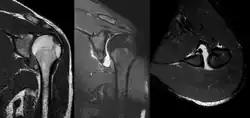

MRI of shoulder after dislocation with Hill-Sachs lesion and labral Bankart's lesion.

In young adults engaged in highly demanding activities shoulder surgery may be considered.[25] Arthroscopic surgery techniques may be used to repair the glenoidal labrum, capsular ligaments, biceps long head anchor or SLAP lesion or to tighten the shoulder capsule.[26]

Arthroscopic stabilization surgery has evolved from the Bankart repair, a time-honored surgical treatment for recurrent anterior instability of the shoulder.[27] However, the failure rate following Bankart repair has been shown to increase markedly in people with significant bone loss from the glenoid (socket).[28] In such cases, improved results have been reported with some form of bone augmentation of the glenoid such as the Latarjet operation.[29][30][31]